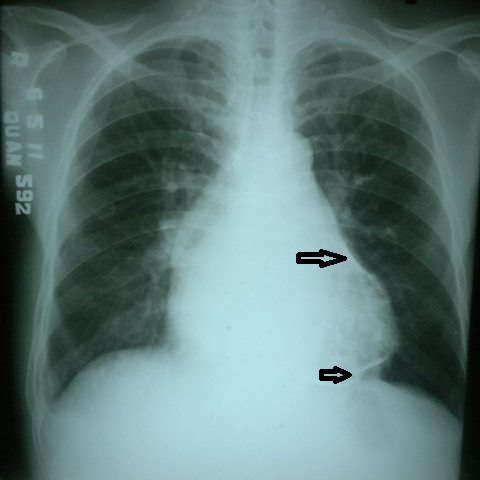

Vôi hóa màng ngoài tim